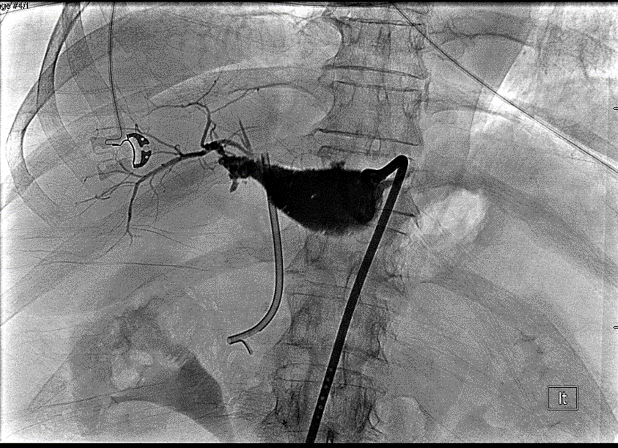

In the IR/GI suite the ERCP scope was advanced to the major papilla under general anesthesia. A glidewire was inserted into the CBD and then passed into the cystic duct. The wire was advanced through the cystic duct through the biloma and into the right posterior ductal system. The IR team had access to the intra-hepatic ducts already through the previously placed PTBD and they percutaneously advanced a snare under fluoroscopic guidance towards the endoscopist's wire to capture the wire and pull it back out the PTBD skin site (see Figure 5 for cholangiogram image). A PTBD was then advanced by IR over the guidewire into the duodenum (Figure 6) and secured into place. Final cholangiogram image showed contrast injected percutaneously traveling through the previous biloma without contrast extravasation and into the cystic duct and duodenum (Figure 7).

Figure 5. Cholangiogram image taken during combined IR/GI rendezvous procedure. An ERCP wire (thin arrow) was fed up through the cystic duct into the right posterior section, where PTBD was already in place. An IR snare (thick arrow) was used to capture the ERCP wire.

Figure 6. A PTBD tube was advanced across the biloma and into the cystic duct down into the duodenum by the IR team.

Figure 7. Final rendezvous cholangiogram showing flow through PTBD through the previous biloma cavity, cystic duct and CBD, finally into the duodenum.